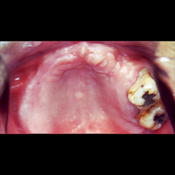

上顎には8本のインプラント体に、ボーンアンカードフレームに取り付けた人工歯が装着されています。

下顎にも前歯部から左奥にかけて8本のインプラント体が埋入され、ヒーリングアバットメントが装着されています。